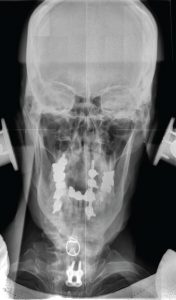

There’s a lot to measure here.

The X-ray is what allows us to measure the misalignment – its direction, complexity and severity–not to mention the detection of physical variations in an individual’s anatomy that may cause a practitioner to refrain from adjusting at all or modify an adjustment in order to provide for the safety of the patient.

For comparison, we can use data from the ADPH X-ray Compliance Branch Office of Radiation Control which reports that the average A-P (front-to-back) cervical X-ray in a chiropractic office is equal to about 78 mrem.